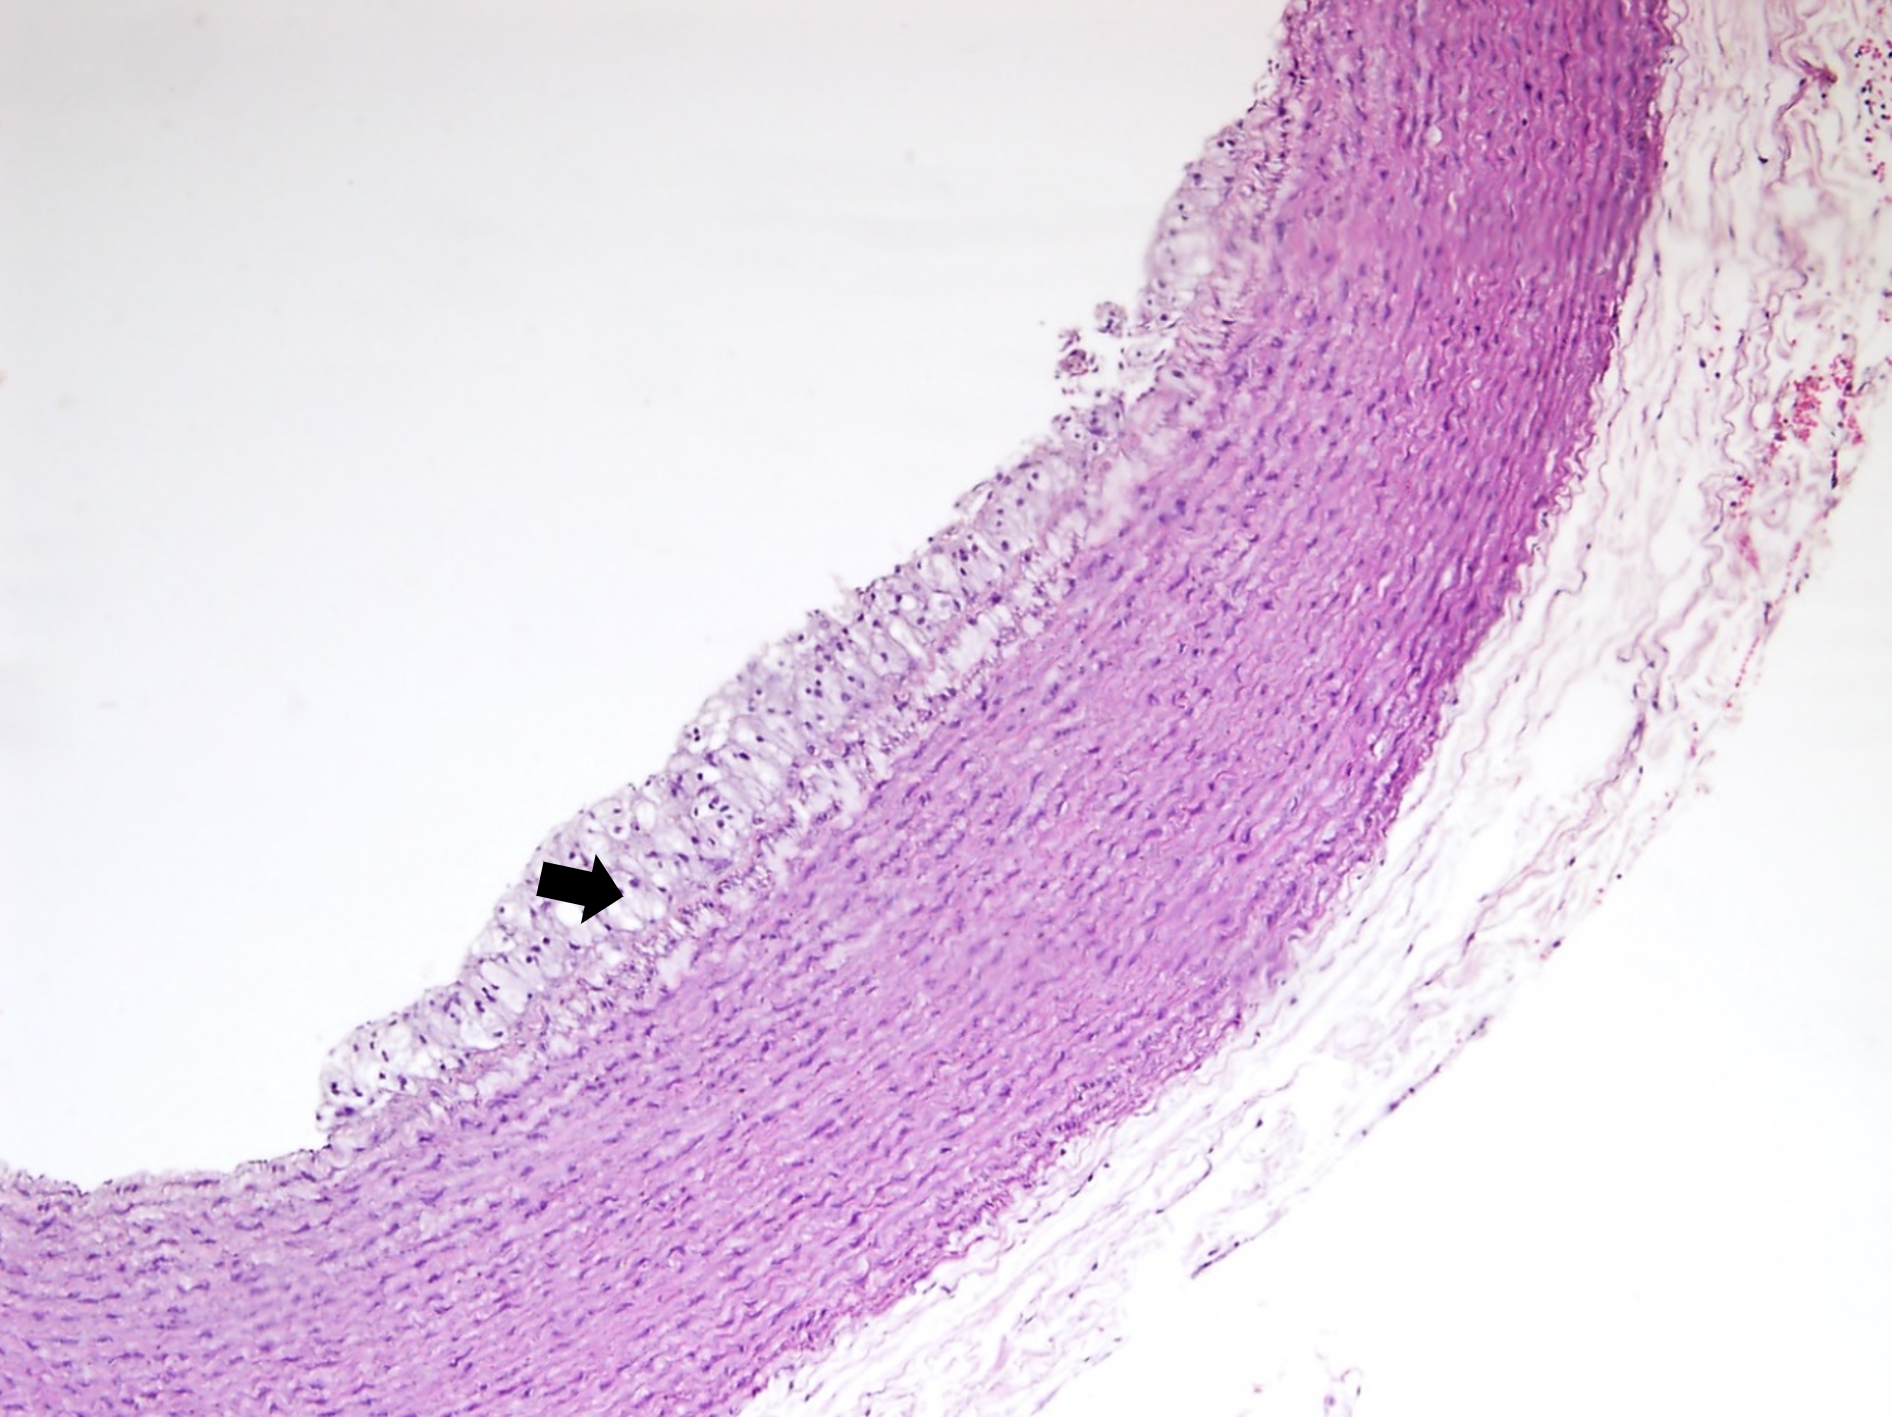

The histological examination of aorta in group A, the control group showed intact tunica intima with thin wavy corrugated endothelium, a normal subendothelial layer, and wavy internal elastic fibers. The tunica media is comprised of elastic fibers and smooth muscle. The outermost layer is the tunica adventitia and is made up of loose connective tissue (Figs. 7,8). In group B, the tunica intima showed the presence of focal thickening, filled with vacuolated cells or foam cells, resulting in the widening of the subendothelial layer (Fig. 9). The tunica intima of the aorta in group C showed intimal thickening with subendothelial collection of foam cells as well as formation of a lipid core and fibrous cap (Fig. 10).

Fig. 7.A photomicrograph of a section of the aorta in group A stained

by hematoxylin and eosin (10